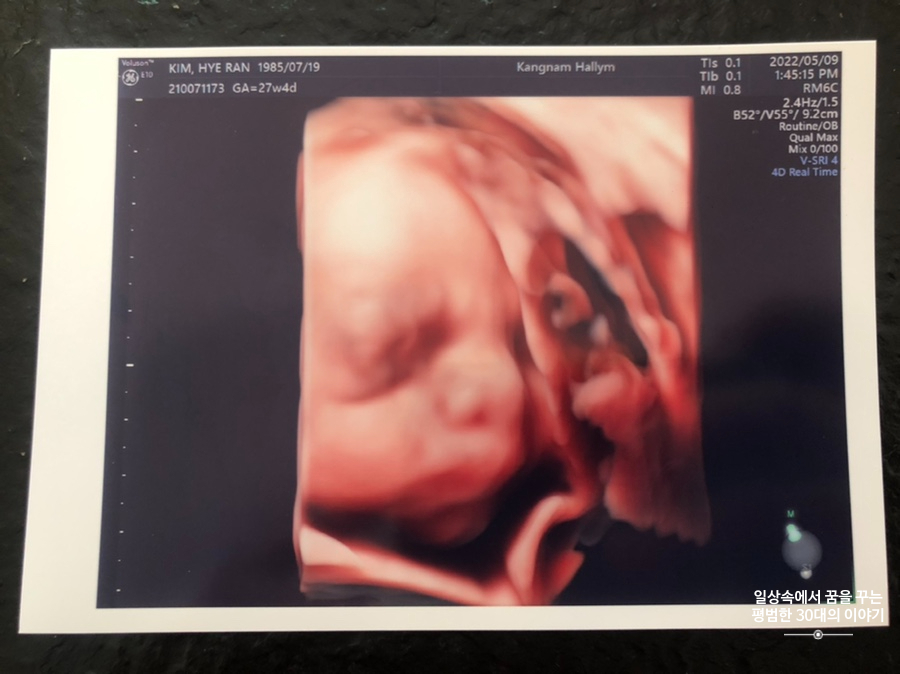

오늘은 입체 초음파 보는 날!!! 입체 초음파는 처음인데다 3주 만에 이안이 얼굴을 본다 생각하니 무척 설레는 마음으로 병원에 갔다. 첫 번째 시도에서는 계속 내 등 쪽으로 얼굴을 대고 엎드려 있어 실패! 초코우유 먹고 열심히 걸은 후, 30분 뒤에 다시 진행한 두 번째 시도에서는 얼굴 반쪽을 보여줬다. 얼굴 전면을 보지 못해 너무 아쉬웠지만 그래도 손가락 빨고 있는 모습, 웃고 있는 모습, 입 뻐끔 거리는 모습, 발차기 하는 모습, 손가락 쥐었다 폈다 하는 모습, 손을 휘적휘적 거리는 모습 등 다양한 모습을 보여줘서 그것만으로도 충분히 만족스러웠다. 내가 다니고 있는 강남성심병원은 입체 초음파가 다른 병원에 비해 무척 비싼 편인데(진료비 내역을 보니 초음파 진단료가 129800원 나옴) 그나마 위안을 삼을 수 있는 것은 화질이 그나마 좋은 편이라는 것이다.